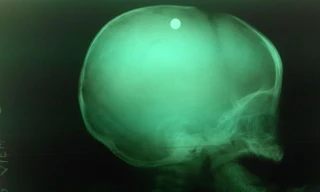

TPO - Lúc 23h ngày 22/3, tại Bệnh viện Chợ Rẫy (Thành phố Hồ Chí Minh), ông Huỳnh Văn Nén, “người tù thế kỷ” đang được chụp cắt lớp (CT) để xác định tình trạng chấn thương sọ não. Bà Nguyễn Thị Cẩm, vợ ông Nén cho biết.